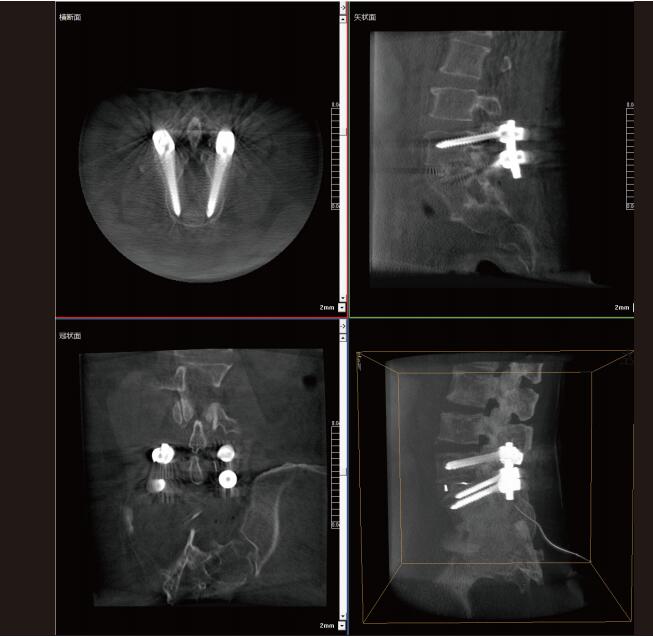

大功率平板三維C形臂PLX C7600術(shù)中實時生成:橫斷面、矢狀面、冠狀面及三維影像,可在任意切面、任意角度評估植入物和解剖結(jié)構(gòu)的相對位置,在手術(shù)室中即可完成結(jié)果的檢查確認(rèn),適用于全身各個部位。